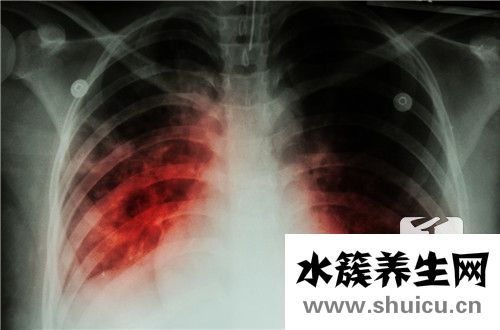

肺炎在臨床上是一種相對復雜的疾病。它可以根據(jù)不同的情況進行分類,包括大葉性肺炎。這種疾病的原因相對復雜,主要是細菌感染,尤其是鏈球菌感染。據(jù)介紹,大葉性肺炎是春季最常見的疾病,也是兒童最常見...